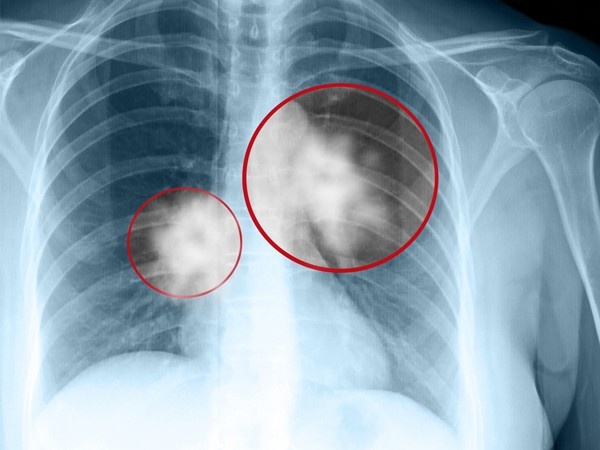

Bệnh ung thư phổi là nguyên nhân hàng đầu gây tử vong do ung thư ở nam giới. Ảnh: Onmed.gr. |

Theo các chuyên gia, ước tính đến năm 2020, số ca mắc mới ung thư phổi cả hai giới mỗi năm tại Việt Nam là hơn 34.000. Đặc biệt, theo PGS.TS. Nguyễn Thị Tuyết Mai, Bệnh viện K (Hà Nội), chỉ khoảng 30% bệnh nhân ung thư phổi không tế bào nhỏ được chẩn đoán ở giai đoạn sớm (giai đoạn 1,2). 70% bệnh nhân được chẩn đoán ở giai đoạn muộn (giai đoạn 3,4). Vì thế, dù có nhiều bước tiến trong chẩn đoán và điều trị, ung thư phổi vẫn thường có tiên lượng xấu và tỷ lệ sống thêm 5 năm khá thấp.

Dựa vào đặc điểm mô bệnh học, Tổ chức Y tế thế giới (WHO) chia ung thư phổi thành 2 loại chính: Ung thư phổi không tế bào nhỏ (Non-Small Cell Lung Cancer) và ung thư phổi tế bào nhỏ (Small Cell Lung Cancer). Trong đó, ung thư phổi không tế bào nhỏ chiếm khoảng 85% các ca ung thư phổi.